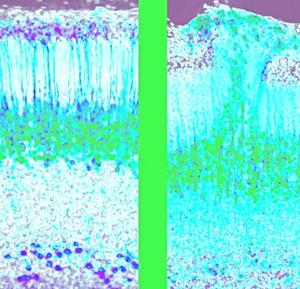

Descubren en ratones un nuevo circuito cerebral embrionario